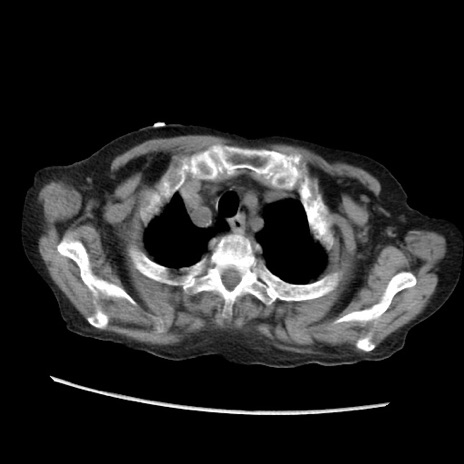

症例31(横断像)

【症例】80歳代 女性

【主訴】腹部膨満感

【現病歴】他院にて肝硬変にてフォロー中。1週間前から便秘、腹部膨満感、臍部腫瘤あり受診となる。

【既往歴】肝硬変

【身体所見】腹部膨隆あり、皮膚変化なし、疼痛なし。

【データ】WBC 4600、CRP 0.25